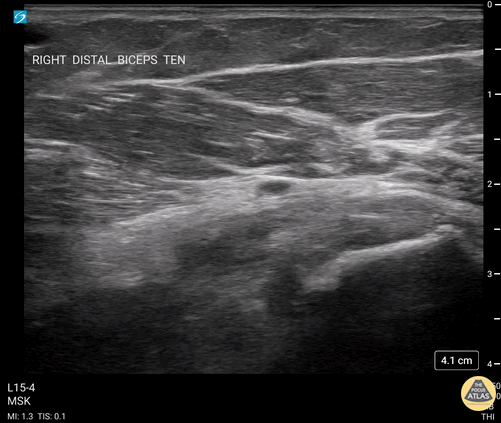

Musculoskeletal - Biceps Tendinosis

60 y/o F w/R elbow pain for 8 months found to have distal biceps tendinosis. L=proximal; R=distal. Medial long-axis view of distal biceps tendon. Radial artery seen pulsating directly superficial to biceps tendon. Distal biceps tendon diffusely thickened with decreased echogenicity at its attachment site. Contributor: Eben Alexander, DO Devesh Patel, MD Eastern Virginia Medical School